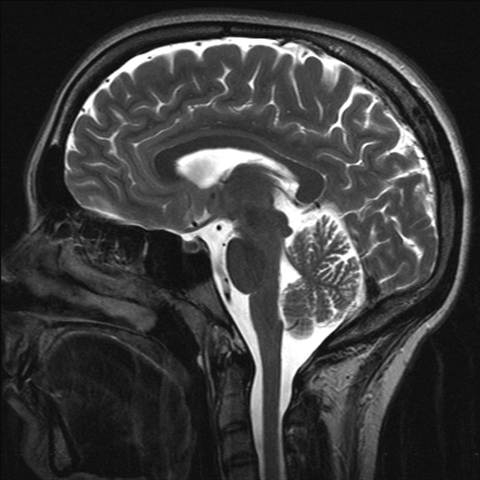

Oamenii își folosesc numai 10 din creier iar activarea celorlalte 90 de procente care sunt adormite le ar permite oamenilor obișnuiți să dea dovadă de abilități mentale extraordinare. Astfel pe bună dreptate se naște întrebarea. Nu există limită pentru ceea ce poate realiza creierul uman. Conţinând aproximativ 100 de miliarde de neuroni creierul este cea mai complexă structură a corpului uman.

Deşi deţine doar 2 din masa totală a corpului vorbim aici de un creier adult acesta consumă 20 din rezervele de energie ale corpului.